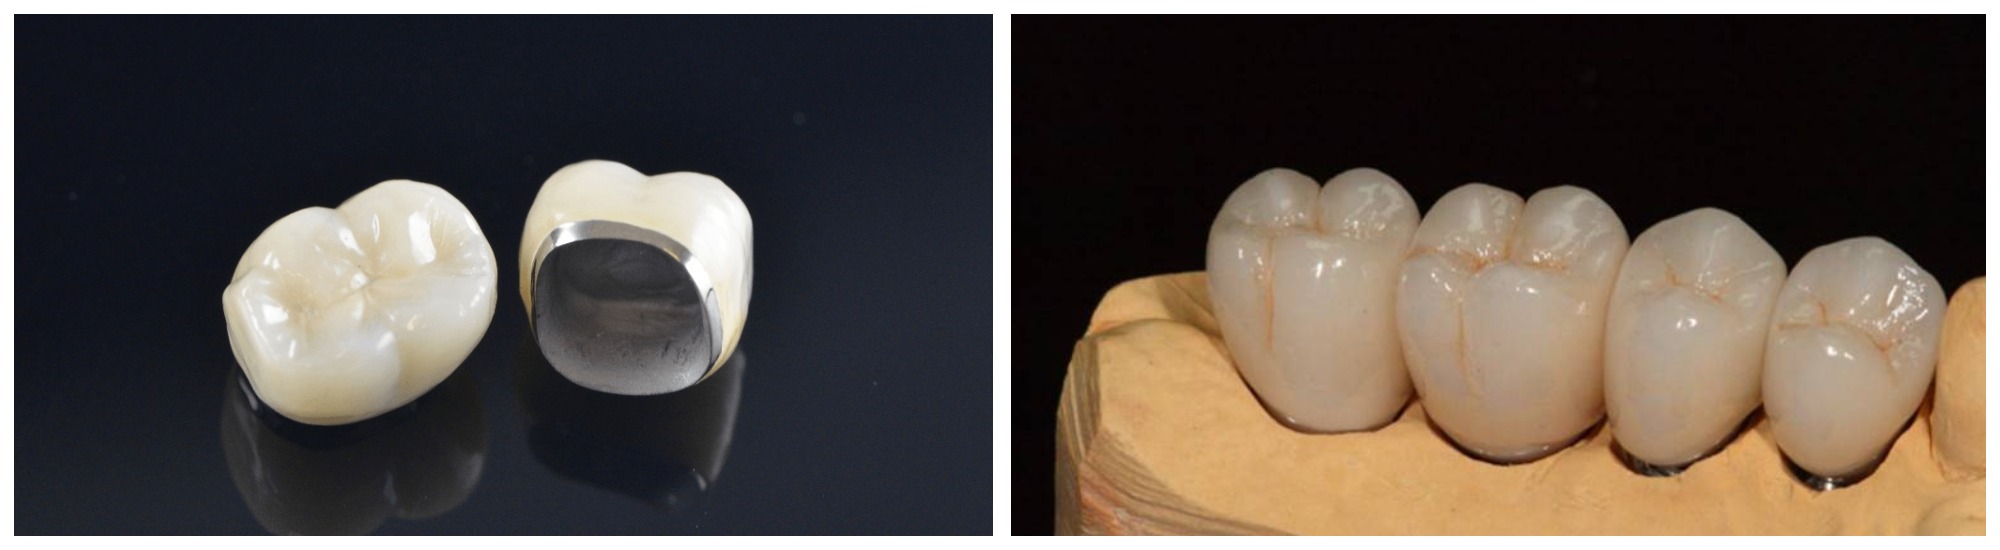

Разновидности зубных коронок и их особенности